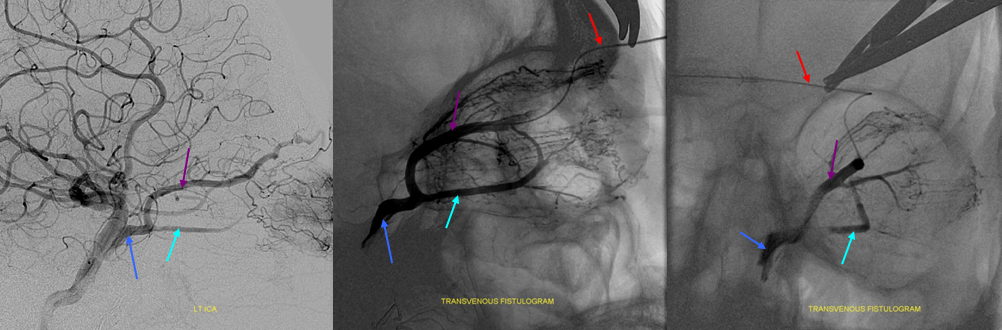

Cavernous Sinus — see also dedicated Cavernous Sinus page

Cavernous sinus is a metaphysical entity. It is a collection of anatomically and functionally separate venous compartment which, altogether, constitute the single venous space we have come to regard as a distinct anatomical structure. It is critical for the neurointerventionalist to understand this, because his or her treatments will be, of necessity, targeting these varied and complex compartments. This is a distinctly different view than the classical question of whether or not the sinus as a whole is involved in a disease process.

Embryologically, although the cavernous sinus is a very early structure, in its earliest form it does not participate in any way in the drainage of the brain — rather collecting tributaries of the future orbital/ophthalmic veins, facial and sphenopalatine systems. Even in the newborn, the connections between sylvian and basal venous systems and cavernous sinus are usually nonexistent — maturation of these connections is one mechanism which allows for stabilization of venous drainage in infants affected by high flow shunts such as some Vein of Galen Malformations. The developmentally late capture of the cavernous sinus by Sylvian and basal veins explains the marked variability in the extent of such capture in adults, while the ophthalmic vein to cavernous sinus connection is essentially constant.

The classical view holds:

Major Tributaries:

1) Basal vein of Rosenthal — typically flows toward CC, but easily reverses flow in cases of fistula, etc.2) Ophthalmic vein — again typically flow is into the sinus, but can easily reverse itself3) Sphenoparietal sinus — also reverses easily. Drains sylvian venous network into the sinus.

Major Egress:

1) Superior Petrosal Sinus

2) Inferior Petrosal Sinus

3) Foramen Rotundum, Foramen Ovale, and other skull base foramina to the pterygoid venous plexus

4) Contralateral Cavernous sinus thru transcavernous channels

5) Clival venous plexus down to foramen magnum region, and from there into jugular veins or marginal sinus. A neat way of projecting arterial phase as a mask for venous phase to demonstrate carotid artery relationship to the cavernous sinus. Many tributaries and egress routes of the cavernous sinus are visible.